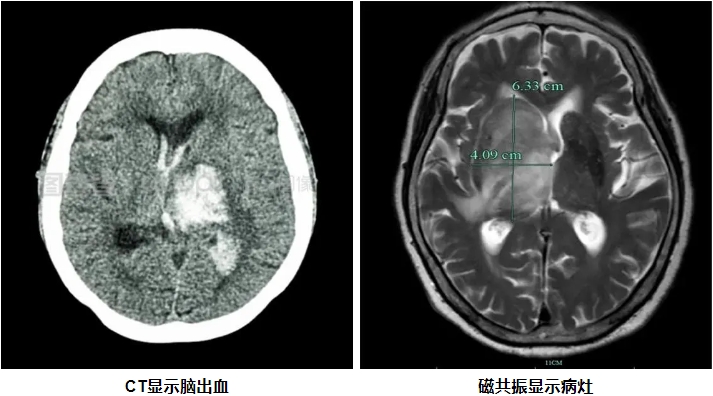

CT与磁共振成像原理及特点 CT检查是利用X线穿透人体后,通过探测器收集数据,再由计算机重建出人体内部结构的图像。它具有成像速度快、密度分辨率高的特点,能够快速发现颅内出血、骨折等病变。然而,CT检查存在一定的局限性,比如对软组织的分辨率较低,且由于颅骨的干扰,后脑病变的显示效果不佳。如果要显示脑血管,需要注射造影剂。 磁共振成像是一种无辐射的检查技术,通过强大的磁场和无线电波脉冲,利用人体内不同组织的磁化反应来成像。它具有多方位、多参数成像的特点,能够提供丰富的组织对比度和详细的解剖信息。磁共振检查在软组织分辨率、图像立体观和抗骨性干扰等方面具有显著优势。 磁共振对后脑病灶显示的优势 后颅窝是脑部的一个重要区域,包括小脑、脑干等重要结构。由于其位置较深,且周围有颅骨的遮挡,CT检查在显示后颅窝病变时往往受到限制。而磁共振检查则能够很好地弥补这一不足。此外,磁共振对软组织的分辨率极高,能够清晰显示小脑、脑干等部位的病变,如脑梗死、肿瘤、脑干病变等。此外磁共振DWI序列能在脑梗死后发生后数分钟就可以发现病灶,而CT需要发病后6-24小时才能发现病灶。尤其是症状表现为头晕,眩晕的患者推荐磁共振检查。 图例: 72岁,男性,突发右侧偏瘫,左侧面瘫,言语含混6小时,CT未见异常,磁共振显示左侧桥脑腹外侧脑梗死。 磁共振评估颅内血管的优势 磁共振血管成像(MRA)是磁共振技术在血管检查中的重要应用。它是一种无创性检查方法,无需注射造影剂,即可获得高分辨率的血管影像。这使得MRA特别适合长期随访的患者以及对造影剂过敏的人群。MRA能够清晰显示颅内动脉的狭窄、闭塞、动脉瘤、动静脉畸形等病变。

为什么做了CT还要做磁共振?